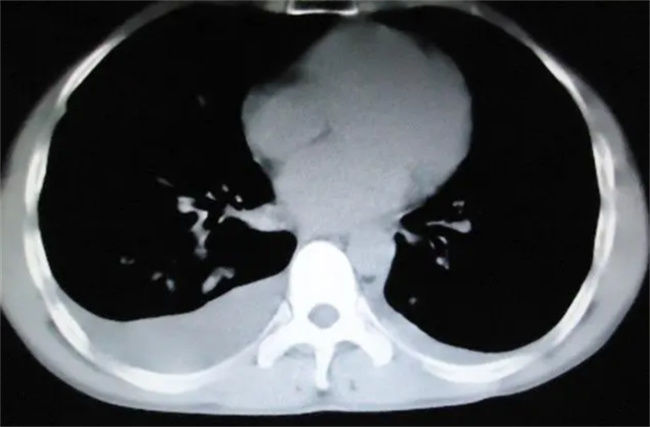

奥密克戎感染之后主要就是发烧,有一些人可能直接就会进入到39度40度,也有一些人可能就会反反复复,有时候高,有时候低,持续的时间或许比较长。如果高烧39度以上持续三天还没有退烧,这就应该引起重视,虽然体温并不是很高,但肺部有可能已经渗出。建议来到医院去检查一下,可以拍摄肺部CT,如果有基础性疾病,高烧超过三天就容易会转变成肺炎,更应该第一时间到医院去拍摄CT,以免出现不必要的影响留下隐患。